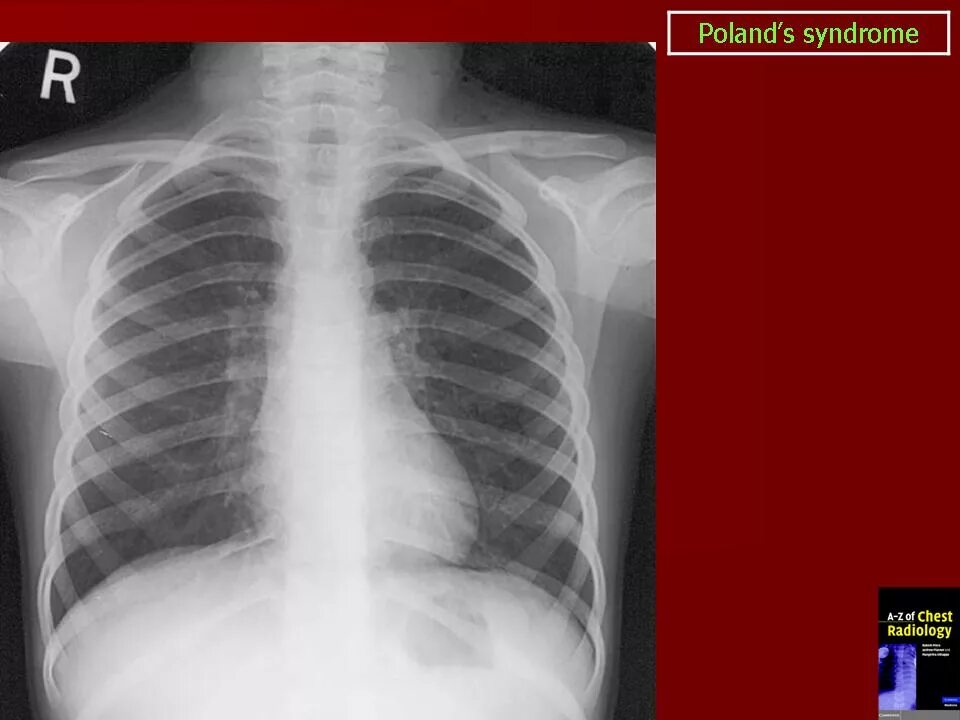

Мышечный дефект